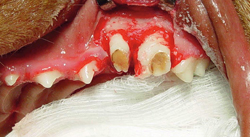

Canine dental implant

Figure 2A: Threaded implant in osteotomy site

Figure 2B: Postop radiograph showing implant in position

After one year, the implant should have integrated sufficiently that restoration can be considered for esthetic reasons if the restored implant is not being overloaded.

Pictures shown are cases presented by Rocco Mele, DVM, of Tucson, Arizona, depicting a successful upper fourth premolar extraction, implant placement and bone graft performed on a dog at the same time and a second case of a canine extraction, implant and bone graft at the same time in a cat.